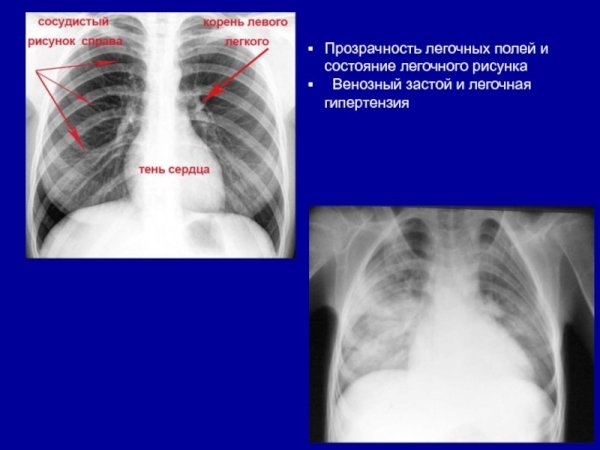

Усиление сосудистого рисунка легких у ребенка может быть признаком различных патологий и состояний. Это визуальное изменение на рентгеновских снимках обычно связано с увеличением притока крови в сосуды легких, что может указывать на наличие воспалительных процессов, инфекций или аллергических реакций. Также это наблюдается при повышении давления в легочной артерии, что может быть вызвано сердечными заболеваниями или другими патологиями системы кровообращения. В любом случае, обнаружение усиленного сосудистого рисунка легких у ребенка требует дополнительного обследования и консультации с педиатром или пульмонологом для постановки точного диагноза и назначения соответствующего лечения.